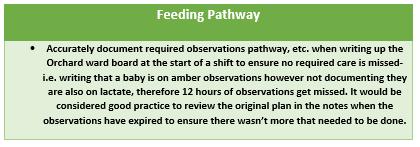

The run chart below shows the data in over the past 2 months. It was pleasing to see the upward trend this month of all areas.

The final figures for January are as follows ;

Skin to Skin =86.5%

Number of babies who received breastmilk = 82.1%

The data shows our monthly figures for skin to skin can vary quite considerably. Please can we ensure all mothers are offered the opportunity to have skin to skin with their baby at delivery (as long as mother and/or baby are clinically well) and this is correctly updated on CMiS